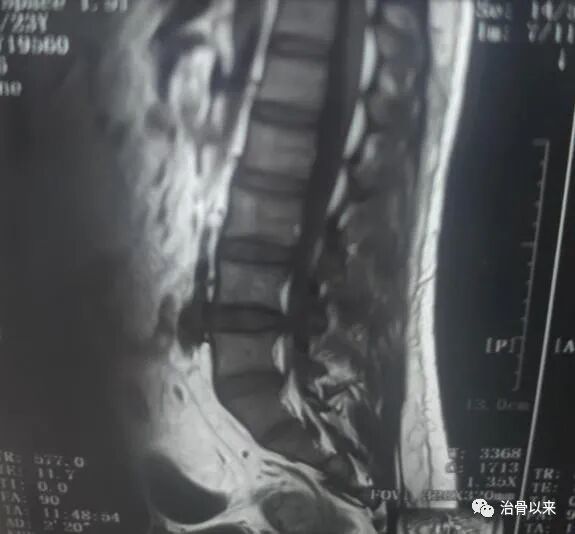

姓名:陈女士疾病:L4-5 腰椎间盘突出症,压迫神经症状:腰痛,小腿酸麻康复方法:中药保守治疗加运动康复患病时间:3年康复时间:3个月左右康复后症状:腰突症状基本消失,腿部恢复正常

最后一次去医院复查X光片,显示我原来突出的第4、5节,有些回纳的迹象。医院的医生都觉得不可思议,一个劲儿的问我到底用了什么办法,怎么效果比手术都好?恢复的和正常的腰椎一模一样!